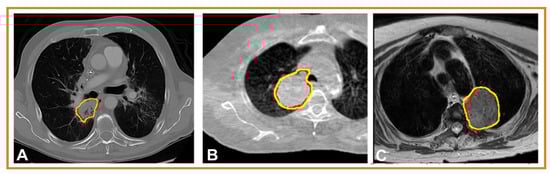

| Jiang J. et al. [59] | Lesion segmentation, detection, and characterization (LSDC) | Original Research: Cross-modality (CT-MRI) prior augmented deep learning for robust lung tumor segmentation from small MR datasets | To develop a cross-modality (MR-CT) deep learning segmentation approach that augments training data using pseudo-MR images produced by transforming expert-segmented CT images. | The advantage of this model is that it is learned as a deep generative adversarial network and transforms expert segmented CT into pseudo-MR images with expert segmentations. | A minor limitation is the number of test datasets, particularly for longitudinal analysis, due to the lack of additional recruitment of patients. |